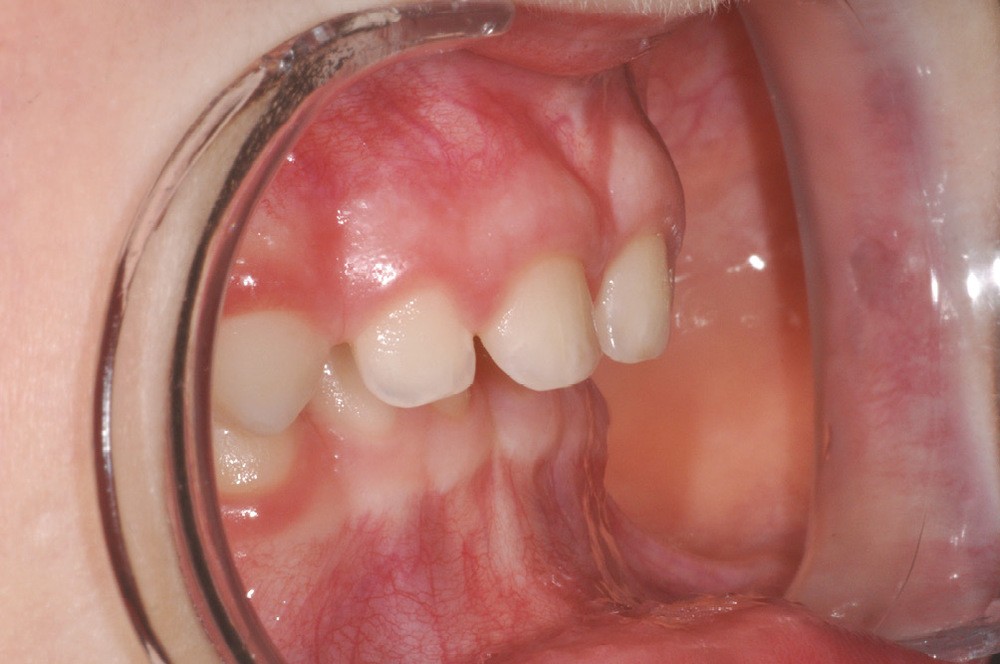

1. Surplomb augmenté chez un enfant de 4 ans.

Deux pics de traumatismes existent : premièrement au moment de l’apprentissage de la marche (avant 18 mois) en raison du manque de coordination motrice et de l’absence de réflexes de protection ; deuxièmement entre 2 et 4 ans avec l’acquisition de la vitesse, l’expérimentation de la sociabilisation et d’une indépendance de mouvement plus grande. Ces accidents surviennent surtout dans la sphère privée [6]. Les traumatismes parodontaux sont les plus fréquemment décrits chez le jeune enfant [7]. 95 % des traumatismes sont localisés au maxillaire et concernent surtout les incisives centrales. Les déformations alvéolaires dues notamment aux habitudes de succion non nutritive (tétine…